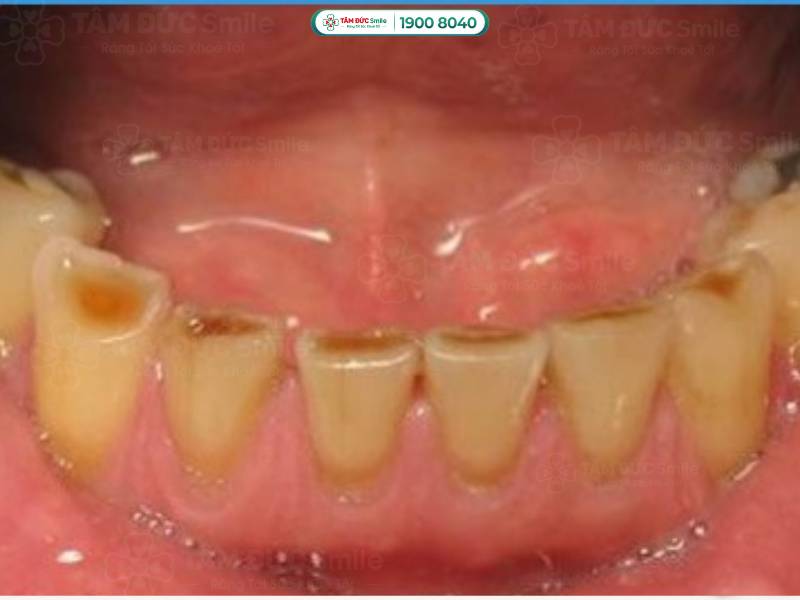

Răng bị mòn mặt nhai là hiện tượng lớp men răng ở phần trên cùng của răng bị bào mòn. Trên mặt nhai xuất hiện các vết lõm nông hoặc sâu không đồng đều, làm mất thẩm mỹ và ảnh hưởng chức năng răng miệng.

Răng bị mòn mặt nhai do mất mô răng. Lớp men răng bảo vệ không còn, cấu trúc của bề mặt nhai có sự thay đổi, bắt đầu xuất hiện các vết lõm. Tùy vào mức độ mòn men răng, vết lõm có thể nông hoặc sâu, làm bạn cảm thấy ê buốt khi ăn nhai.

Mặt nhai của răng bị mòn được chia thành 3 cấp độ từ nhẹ đến nặng:

- Mức độ nhẹ: Chỉ lớp men răng bị mòn, khi ăn đồ nóng hay lạnh, bạn sẽ cảm thấy hơi ê buốt.

- Mức độ nặng: Không chỉ lớp men răng, ngà răng bên trong cũng bị phá hủy. Bạn cảm thấy ê buốt thường xuyên, kèm theo cơn đau nhức ở vị trí răng bị mòn.

- Mức độ cực kỳ nghiêm trọng: Răng yếu, xuất hiện tình trạng lung lay, đổi màu. Nếu bạn không điều trị kịp thời, tủy răng ở sâu bên trong cũng bị ảnh hưởng.

Răng bị mòn mặt nhai là hiện tượng lớp men răng ở phần trên cùng của răng bị bào mòn

1.2.4. Răng bị mòn mặt nhai gây ảnh hưởng lớn đến thẩm mỹ

Lớp men răng bị mất làm cho răng chuyển dần thành màu vàng nâu, rất mất thẩm mỹ. Ngoài ra, răng mất lớp men bảo vệ sẽ ngắn hơn các răng khác. Nếu tình trạng này xuất hiện ở răng cửa, thẩm mỹ nụ cười của bạn sẽ bị ảnh hưởng.